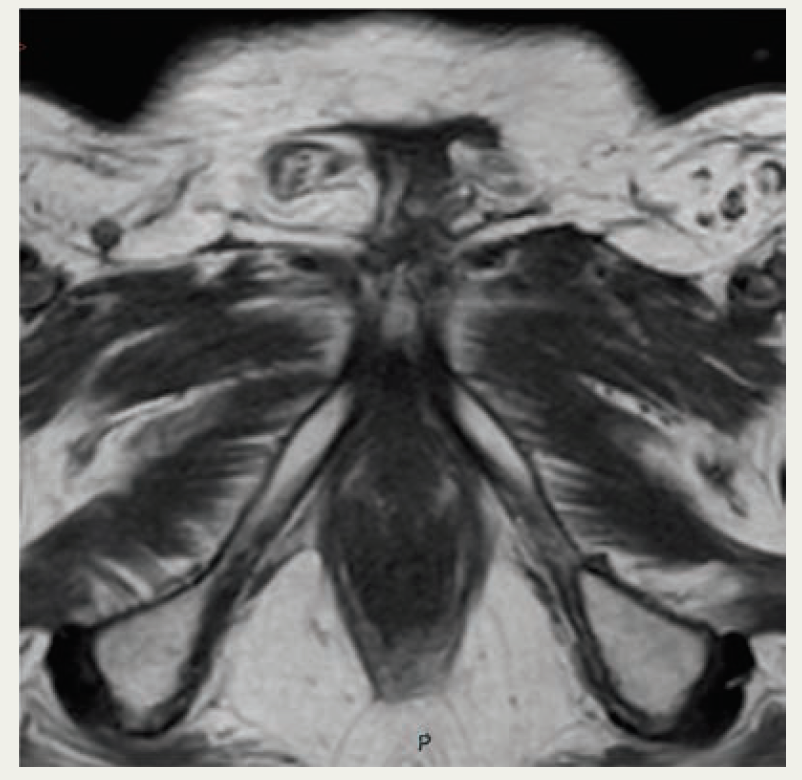

Therefore, treatment was planned with 60 Gy in 30 fractions, with a 6-Gy boost to the primary site using volumetric arc technique, and the use of 1-cm wax bolus covering the gross total volume of the penis and nodes plus margin (Figure 2). MK successfully completed radical radiotherapy with acute grade 2 radiation dermatitis. Initial scans showed a response to treatment, although some of the necrotic residual tumor bed was slow to resolve. The suprapubic catheter was required for ongoing urinary diversion as the tumor shrinkage had essentially resulted in a loss of any normal penile anatomy (Figure 3). Scans continued to show an improvement in the appearance of the tumor bed until there was no discernible remaining cancer. The patient has remained on follow-up for 2 years with no evidence of distant disease or local progression. Of interest, MK developed a transient viral human papillomavirus (HPV) infection in the form of warts at the scrotum 18 months after completing radiotherapy and went on to have HPV immunization.

FIGURE 3. MRI From Most Recent Follow-Up at 2 Years, Demonstrating No Disease